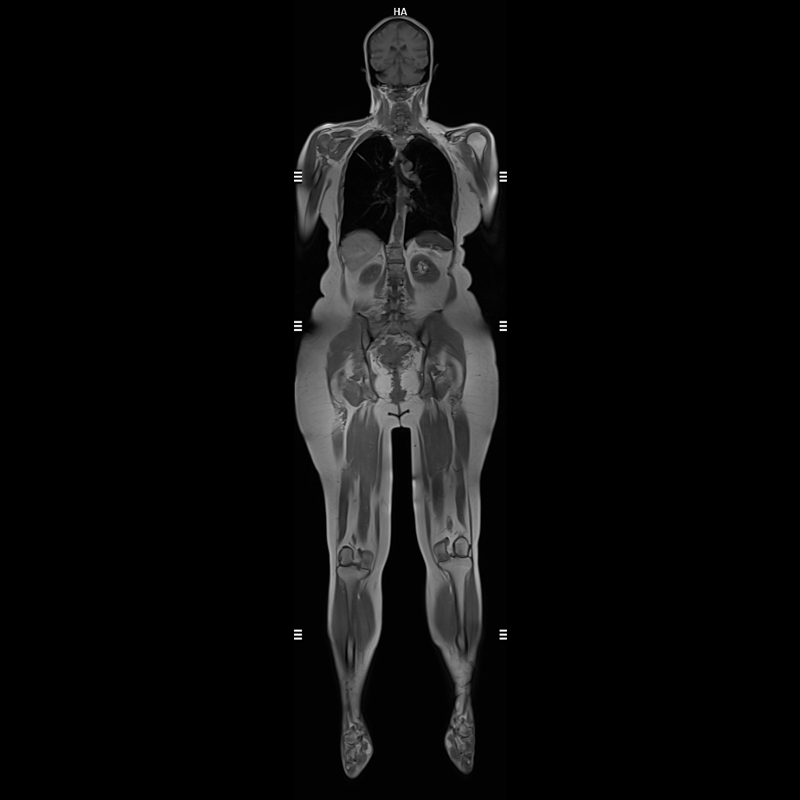

3 Tesla MR Tüm Vücut Görüntülemede Yapay Zeka Destekli Son Teknoloji